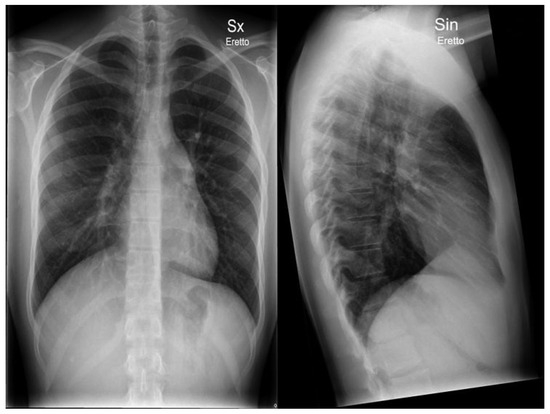

Typical Signs of Secundum Atrial Septal Defect in a Young Man

Case report

- Egeblad, H.; Berning, J.; Efsen, F.; Wennevold, A. Non-invasive diagnosis in clinically suspected atrial septal defect of secundum or sinus venosus type: value of combining chest x-ray, phonocardiography, and M-mode echocardiography. Br Heart J. 1980, 44, 317–321. [Google Scholar] [PubMed]